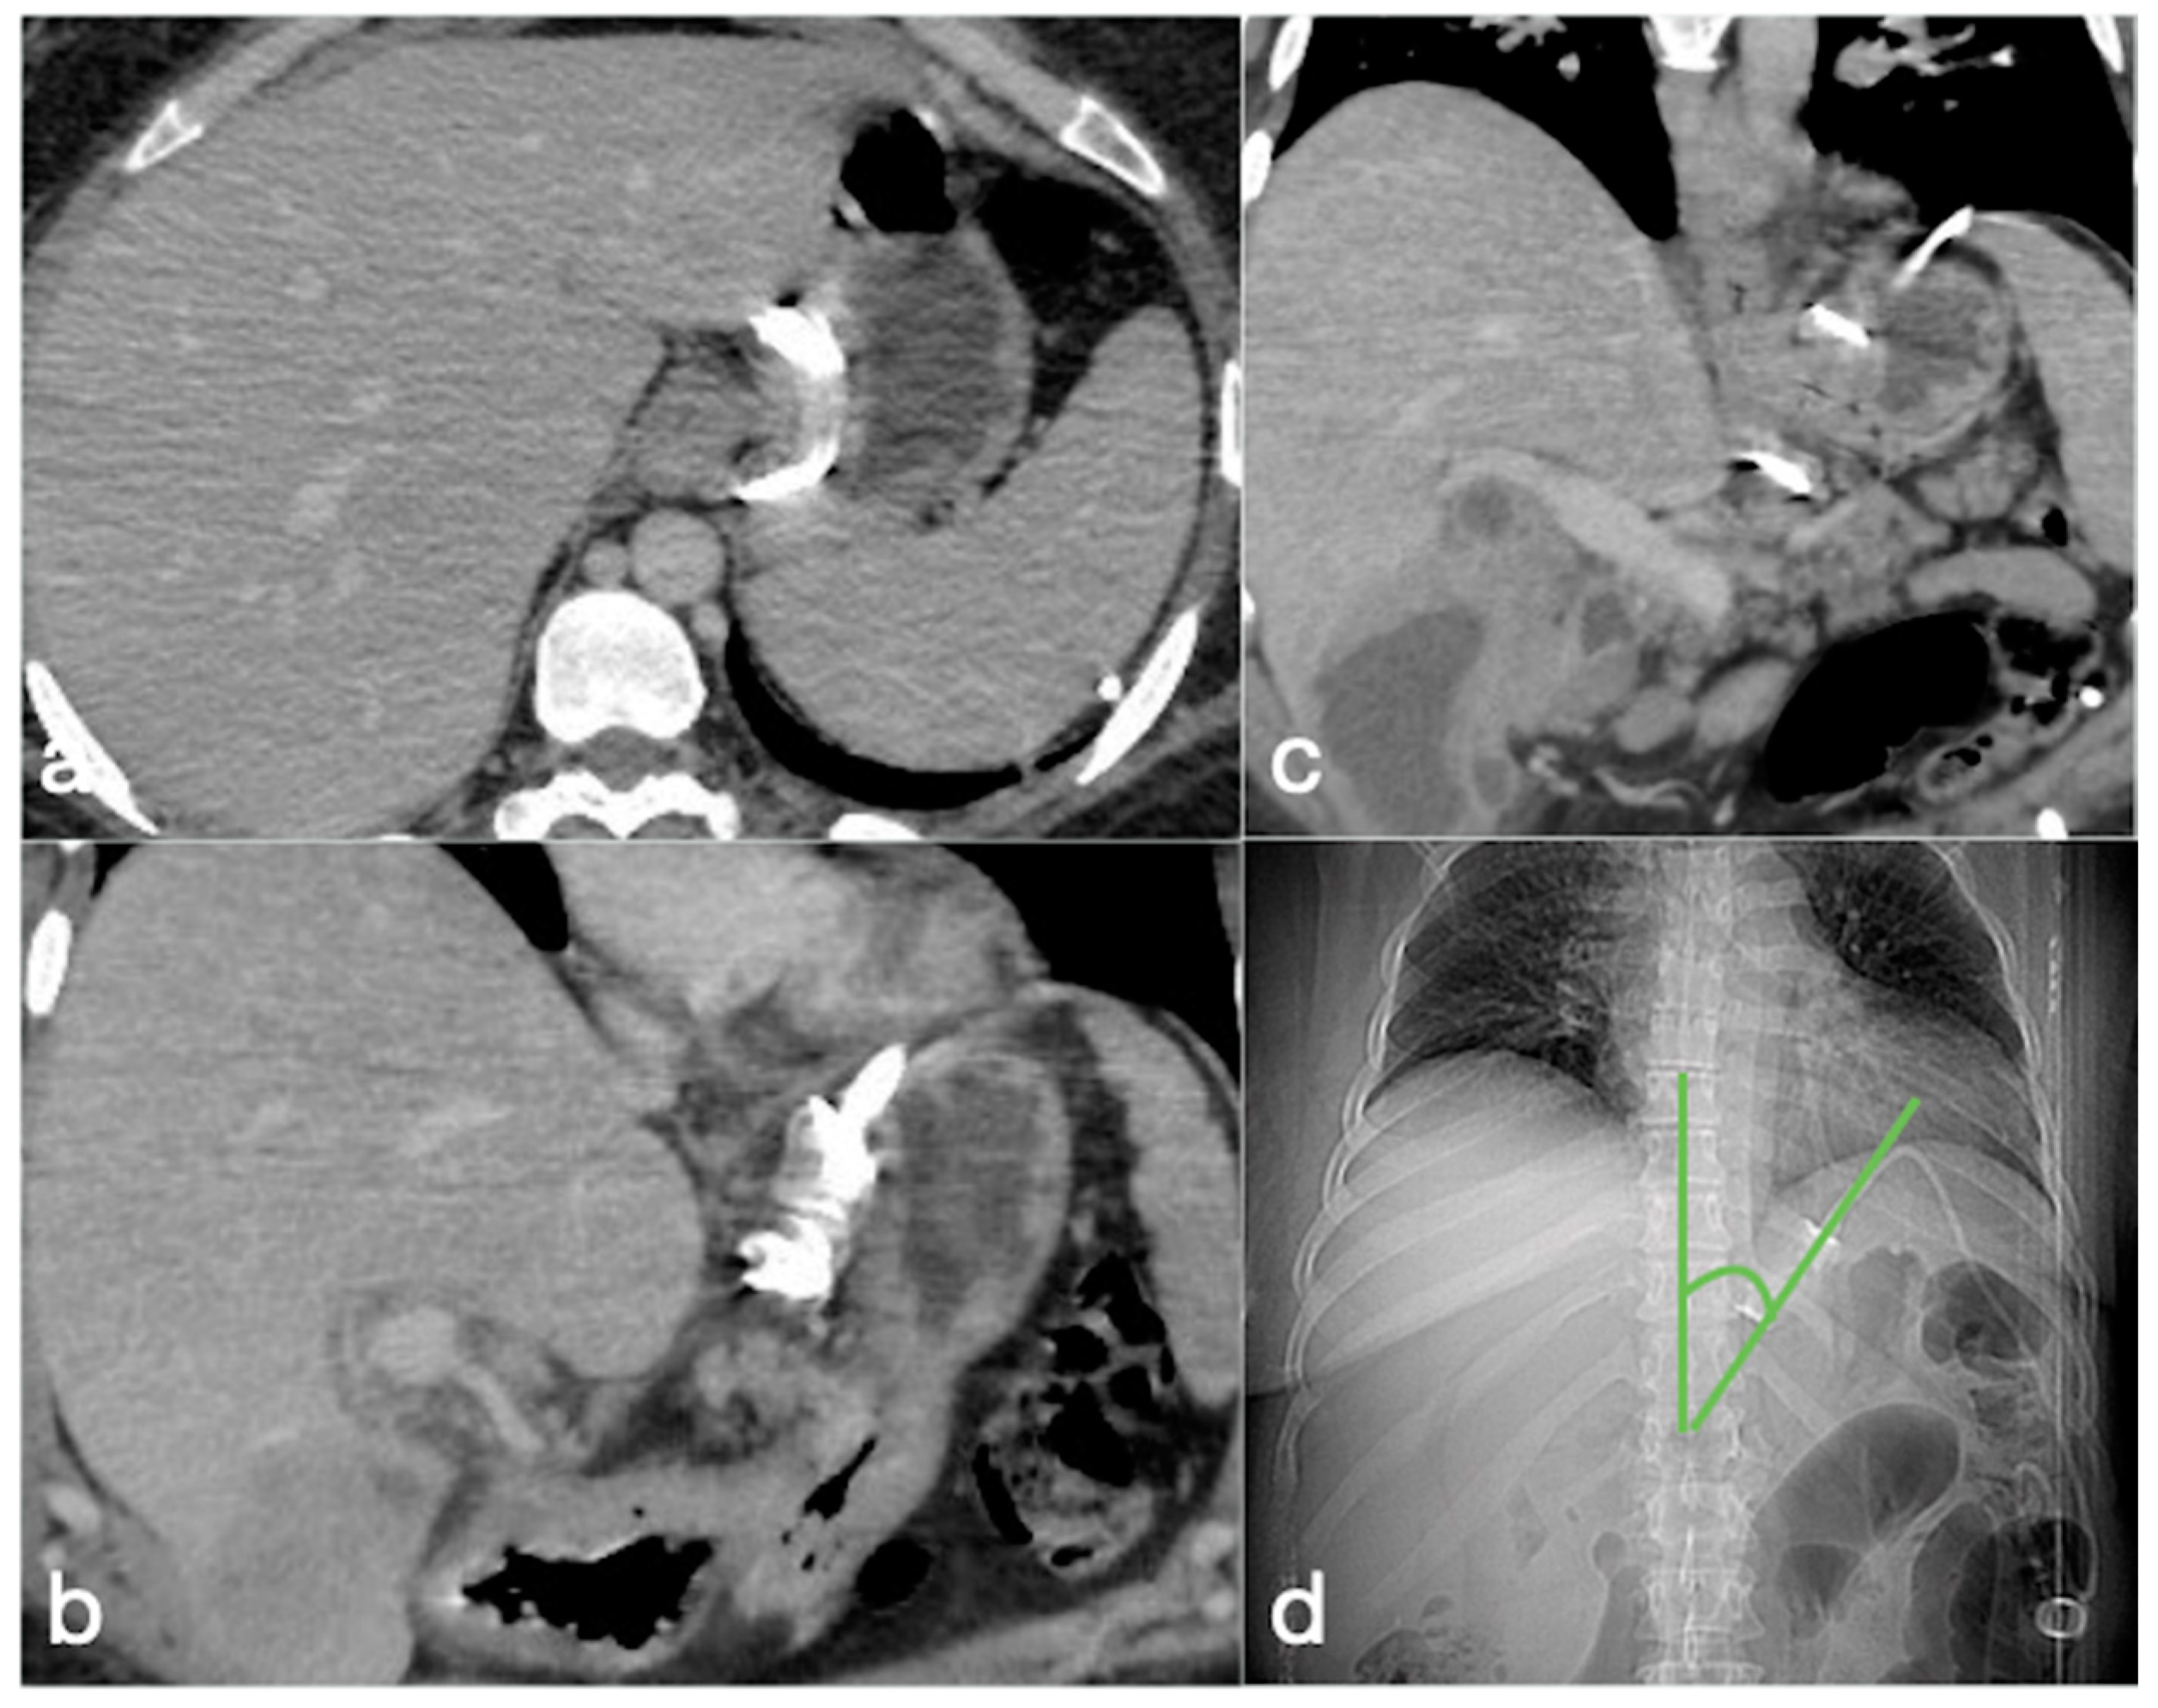

3.3.2. AGB

- Band slippage

- Pouch dilatation

- Device-related

- Erosion

- Acute perforation

- Gastric volvulus